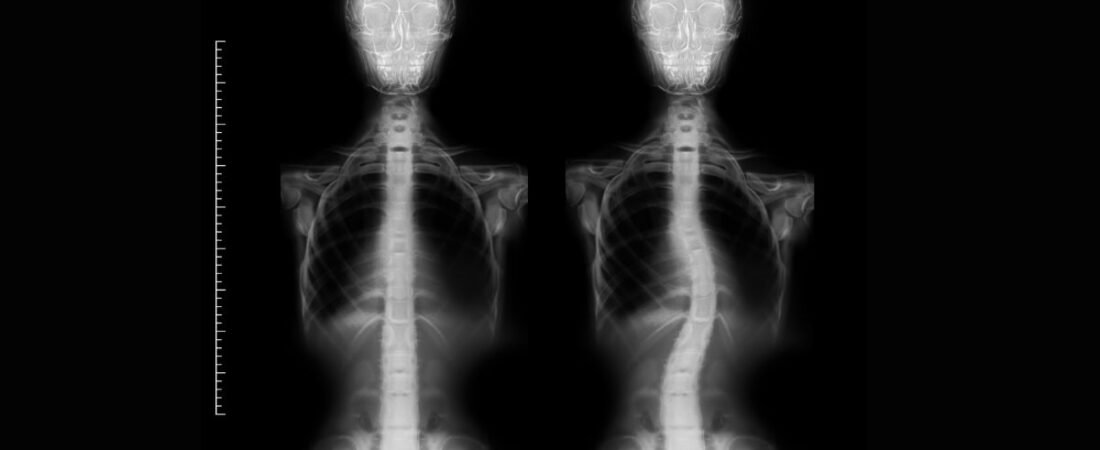

A escoliose é um desvio na curvatura da coluna vertebral, que pode afetar tanto a região lombar quanto o segmento torácico.

Essa curvatura é lateral e vem acompanhada de rotação das vértebras

Esse desvio lateral associado com a rotação das vértebras, faz com que a coluna sofra uma torção em seu eixo vertical.

O diagnóstico da escoliose é feito por meio de uma avaliação clínica detalhada e exames de imagem, especialmente radiografias, que permitem identificar a curvatura da coluna.

Na radiografia, o método mais preciso para avaliar a gravidade da escoliose é a medida do Ângulo de Cobb, que define a intensidade da curvatura:

| Grau da Curvatura | Classificação |

| 11 a 25 graus | Escoliose leve |

| 25 a 45 graus | Escoliose moderada |

| Acima de 45 graus | Escoliose grave |